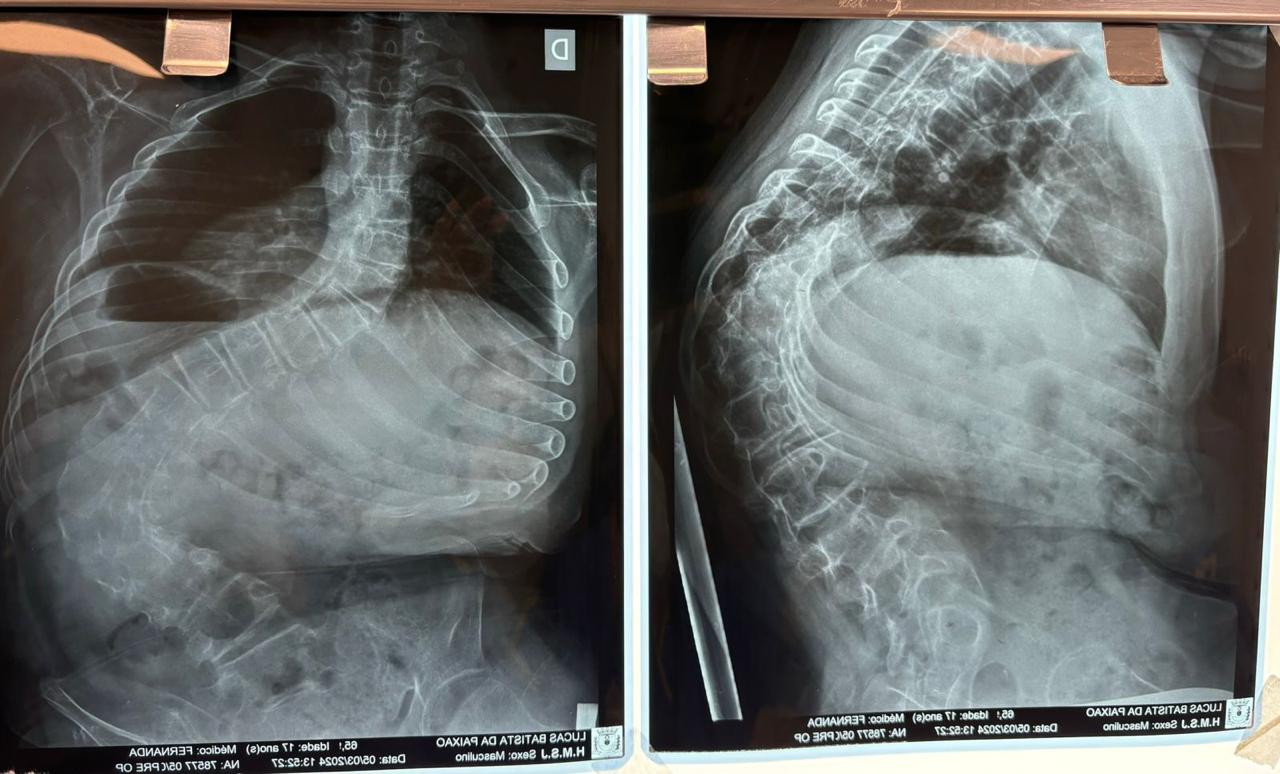

Outro tipo de escoliose é a causada por doenças neuromusculares, como paralisia cerebral, mielomeningocele, distrofia muscular, atrofia muscular espinhal, entre outras. No caso do Lucas Batista da Paixão, de 18 anos, a paralisia cerebral que teve ao nascer foi o que desencadeou a condição.

Com curvatura acima dos 100 graus, desconfortos respiratórios como falta de ar e asma, a posição do adolescente na cadeira de rodas estava bem limitada. Para a mãe de Lucas, Daniele de Oliveira Batista, a cirurgia foi fundamental para melhorar a autonomia e qualidade de vida do filho.

“Foi um longo processo até chegar aqui no CHT, esperávamos por essa cirurgia há mais de dois anos e, depois de tantas dificuldades, hoje conseguimos fazer um passeio sem que ele reclame de dor. Ele também já consegue ficar em muitas outras posições que antes eram desconfortáveis e geravam muita dor. Só temos a agradecer a toda equipe médica pelos cuidados e ótimo atendimento prestado ao meu filho”, disse.